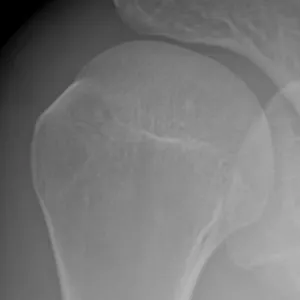

Pour des raisons mal connues (a priori indépendantes du type d’alimentation), des dépôts semblables à de la craie peuvent apparaître au sein des tendons de la coiffe des rotateurs.

- Elles augmentent le risque de rupture tendineuse : proportionnellement à leur taille, elles fragilisent les fibres du tendon.

Ces calcifications sont trop souvent banalisées car elles sont souvent indolores. Malheureusement ces calcifications désorganisent et détruisent à bas bruit les fibres des tendons au sein desquels elles se développent. Laisser grossir ces calcifications augmente le risque de rupture tendineuse lors d’un traumatisme ou d’un effort. Le traitement médical a l’inconvénient de calmer la douleur mais de laisser la calcification grossir à bas bruit. Dès que la taille de la calcification devient conséquente par rapport au tendon, la ponction lavage doit être proposée pour stopper son évolution.